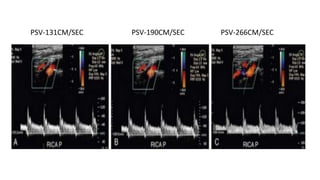

PSV-131CM/SEC PSV-190CM/SEC PSV-266CM/SEC

Pitfalls: Technique • IncorrectChoice of Doppler Angle • Incorrect Gain

• #30 The angle of spectral Doppler insonation should be kept between 45 and 60 degrees to minimize error in the calculation of velocity from the Doppler frequency shift. When the Doppler angle (yellow circles) is 44 degrees (A), PSV is calculated at 131 cm/sec. However, with a Doppler angle of 60 degrees (B), PSV is 190 cm/sec; and when the Doppler angle is 70 degrees (C), PSV is calculated at 266 cm/sec. Thus, an incorrect Doppler angle or variations in Doppler angle from examination to examination can introduce significant error into the measurement of PSV.